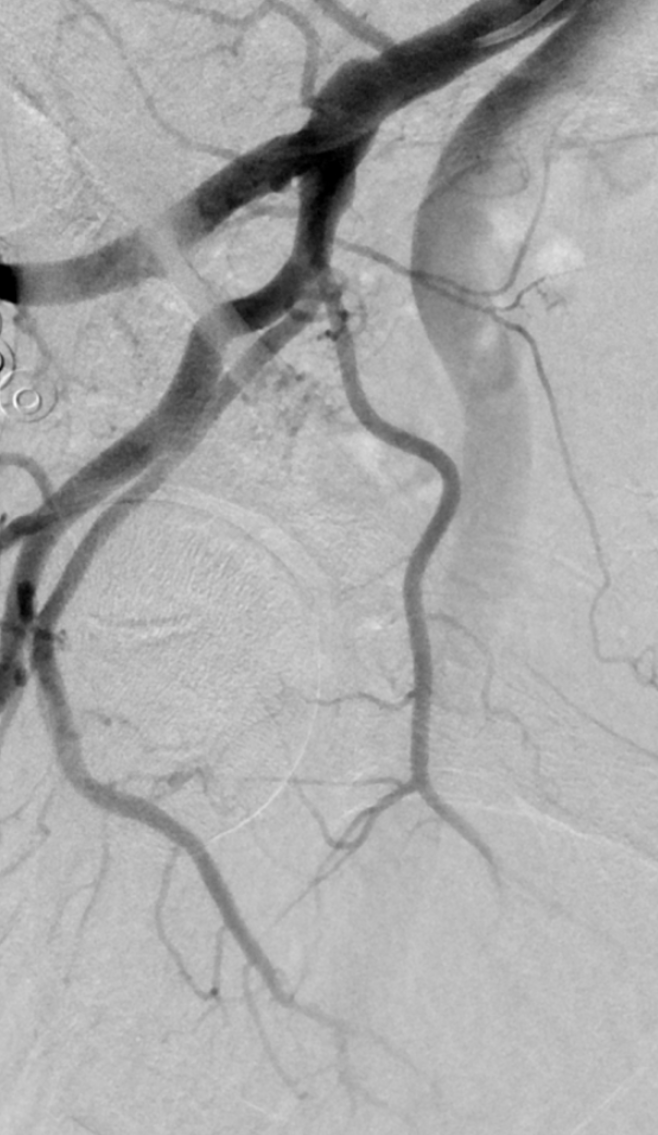

We authored an article for Medical Professionals CLT highlighting Genicular Artery Embolization (#GAE)—an innovative treatment for #kneepain caused by osteoarthritis. #irad @theobserver @wcnc @SIRspecialists